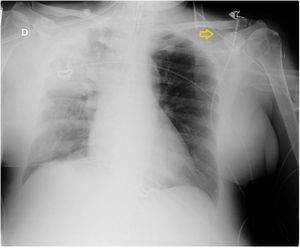

Paciente que ingresa en Unidad de Cuidados Intensivos por neumonía derecha, se canaliza catéter venoso central de inserción periférica (PICC) para tratamiento intravenoso. En radiografía de tórax el catéter no desemboca en aurícula derecha y sigue un trayecto a nivel clavicular (fig. 1). Al 6.° día de ingreso se retira PICC, presentando una celulitis en el cuello a nivel de la yugular izquierda. Realizamos ecografía vascular donde se objetiva una trombosis venosa desde la zona de canalización del PICC en la vena mediana cefálica izquierda (MC), que progresa por la vena cefálica hasta yugular externa por un tramo de comunicación anómala venosa supraclavicular (figs. 2 y 3).